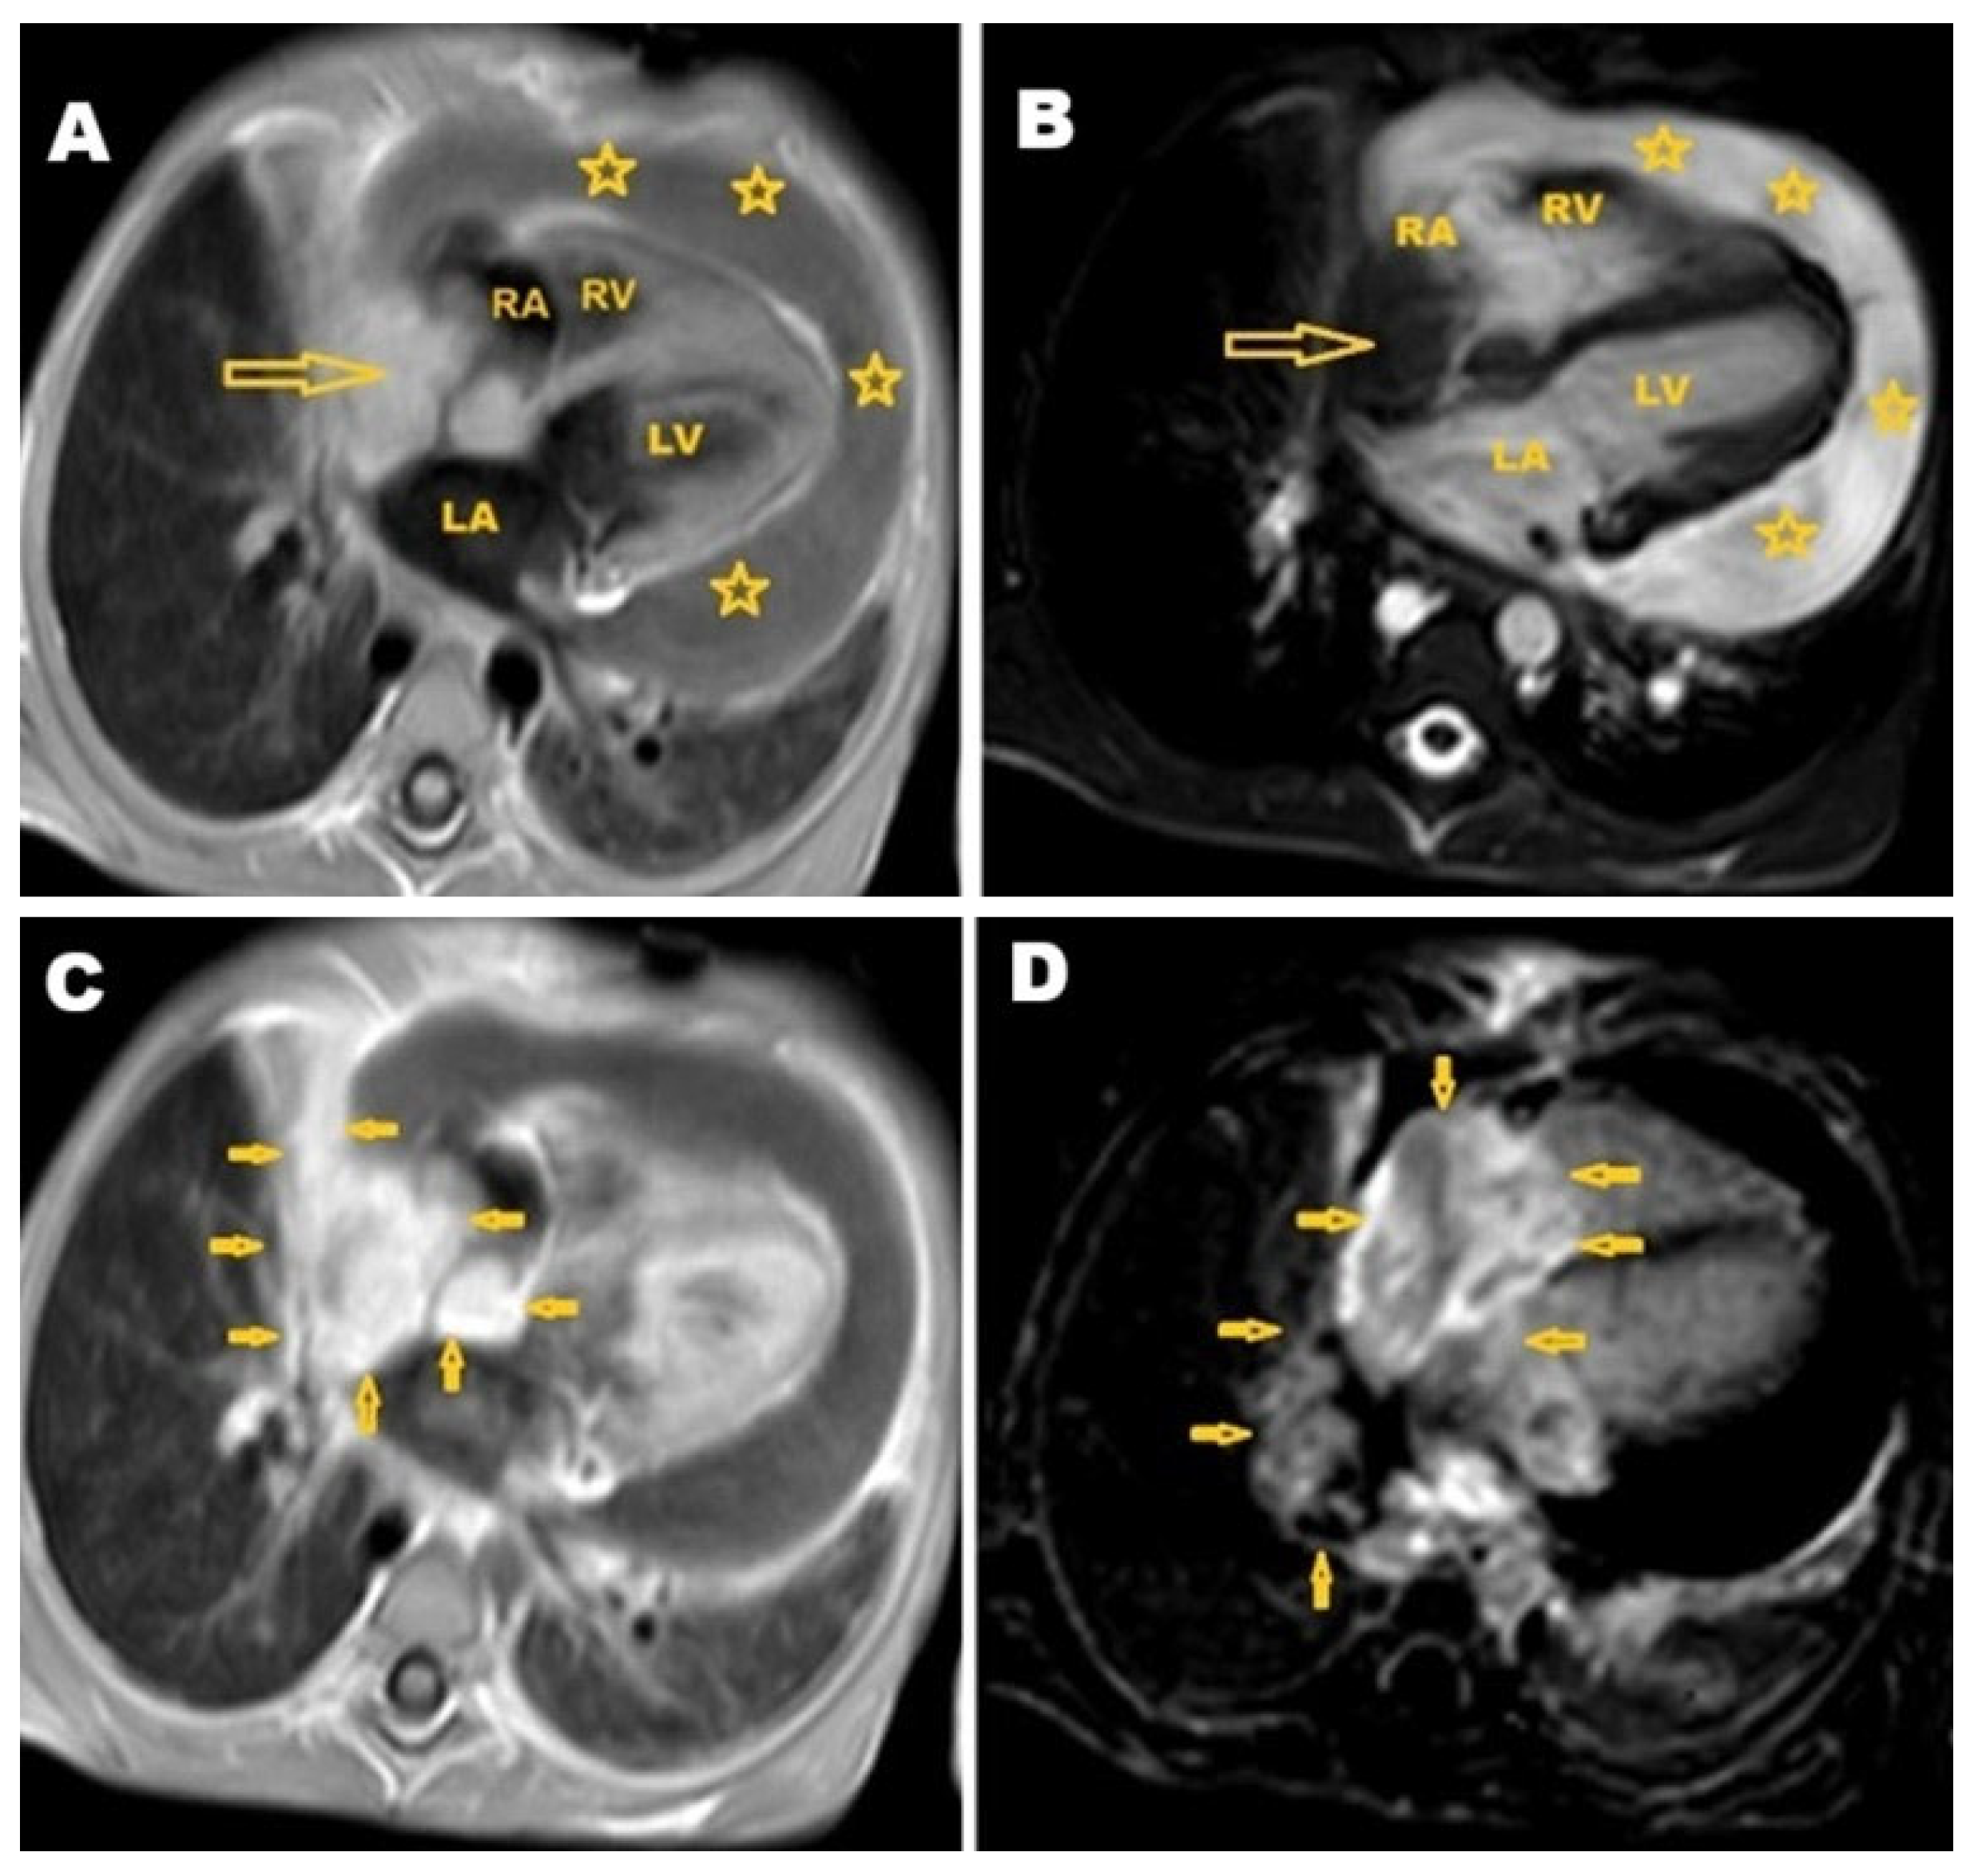

2. Case Presentation